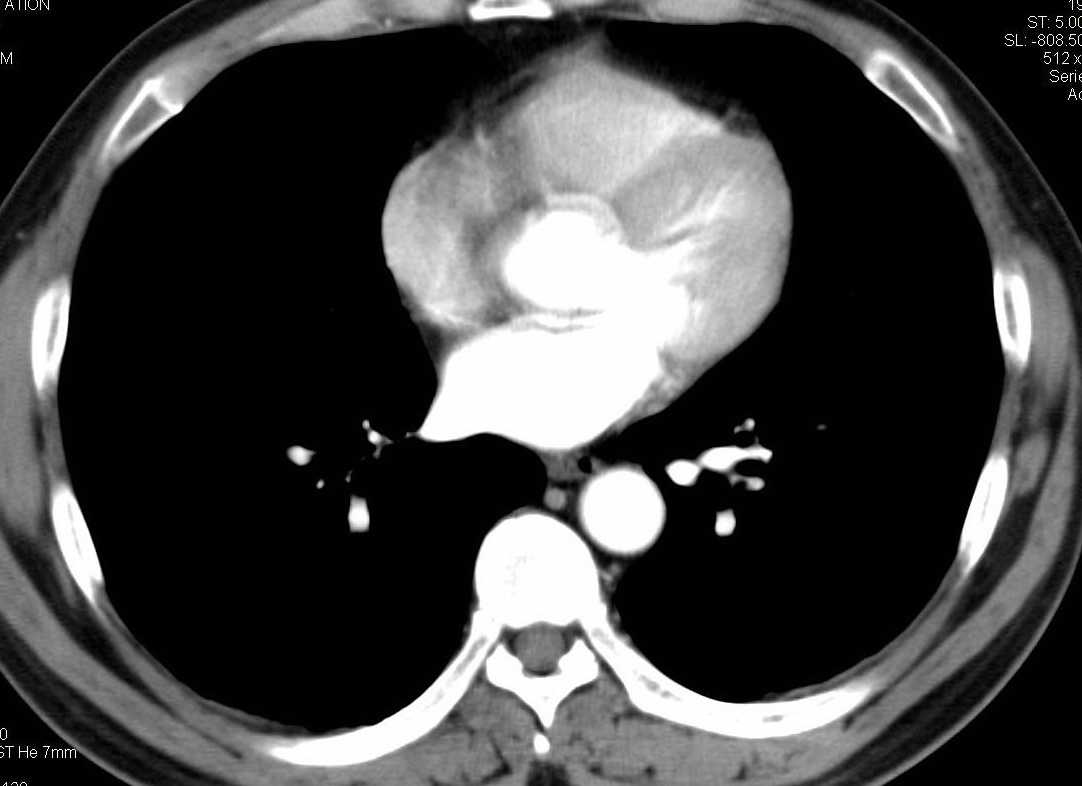

标题: CT15857:男性 58岁 咳痰带血 无发热 请各位大侠发表一下意见 [打印本页]

标题: CT15857:男性 58岁 咳痰带血 无发热 请各位大侠发表一下意见

两肺下叶肺纹理增多、增粗并呈“树芽状”改变。支气管扩张呈囊状,部分呈柱状改变。其周围可见散在的斑片样及条索样密度增高影,右肺下叶近叶间胸膜可见一形态不规则的高密度结节影,并与胸膜粘连。

考虑:支扩并发感染。

双肺间质性改变(间质纤维化?)伴支扩。右肺下叶有毛刺的小结节,考虑周围型肺癌可能性。